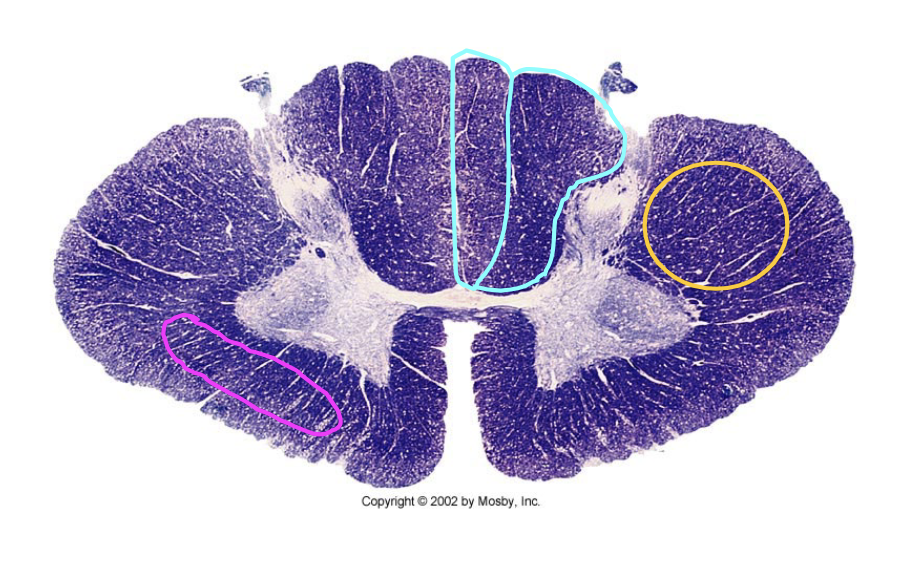

What clinical findings would you expect with each of these lesions?

loss of dorsal column modalatities (ipsilateral)

loss of spinothalamic modalaties on left side

loss of sensation in lower extremeties

bilateral spinothalamic suspended sensory loss

which sensory (ascending) pathway is lesioned here? which motor (descending) pathway is lesioned?

(ascending) spinothalamic = contralateral deficit at level of lesion and below

(motor) corticospinal = ipsilateral deficit at level of lesion and below

(ascending) dorsal column = ipsilateral deficit at level of lesion and below

(motor) none